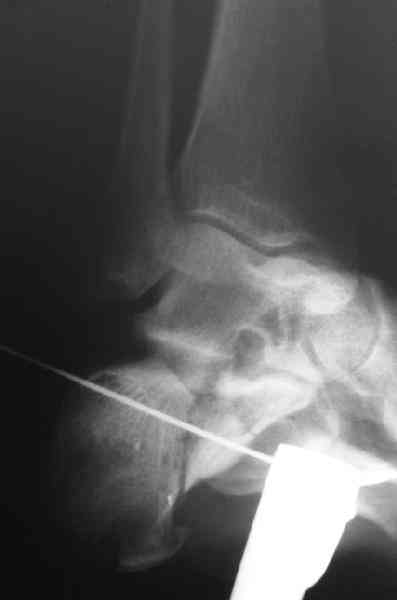

Re: Перелом пяточной кости

Открытый и закрытый способы лечения.